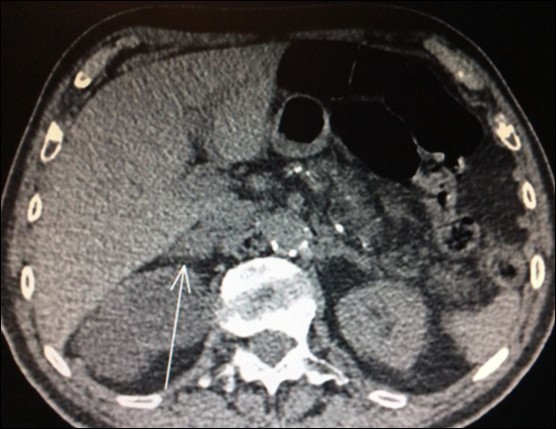

Usually, the imaging screening used for diagnosis of adrenal metastasis are: CT scans (Figure 1), magnetic resonance imaging (MRI) and PET-CT. The sensitivity of PET-CT has conflicting results, being of 96% and with false-positive detection rate even for smaller masses (without swelling and not evident on CT or MRI) of only 4% as reported in some series8,9,18. Another study confirms these findings, showing sensitivity and specificity of PET/CT for distant metastasis of 94% and 85%, respectively31.

Figure 1.CT scan showing isolated right adrenal NSLC metastasis (Arrow)